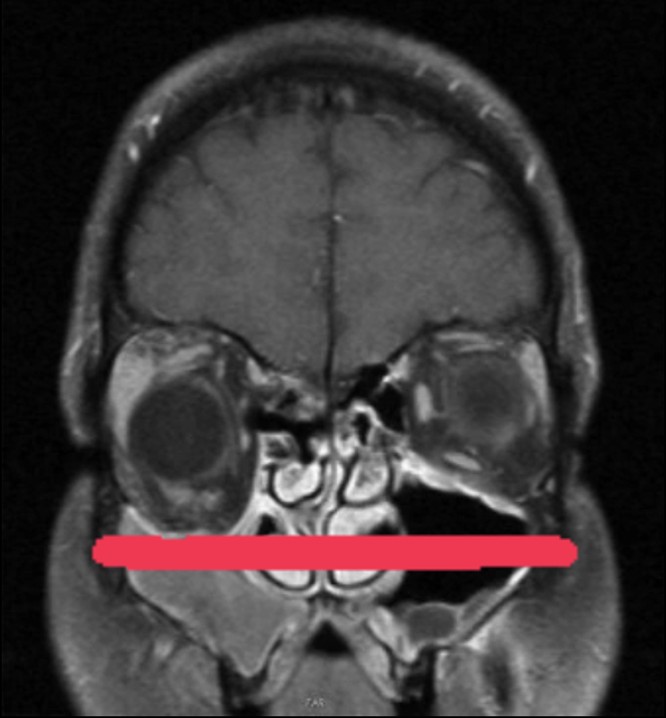

Enolftamia do olho direito

Exame de ressonância magnética com rebaixamento do assoalho da órbita direita